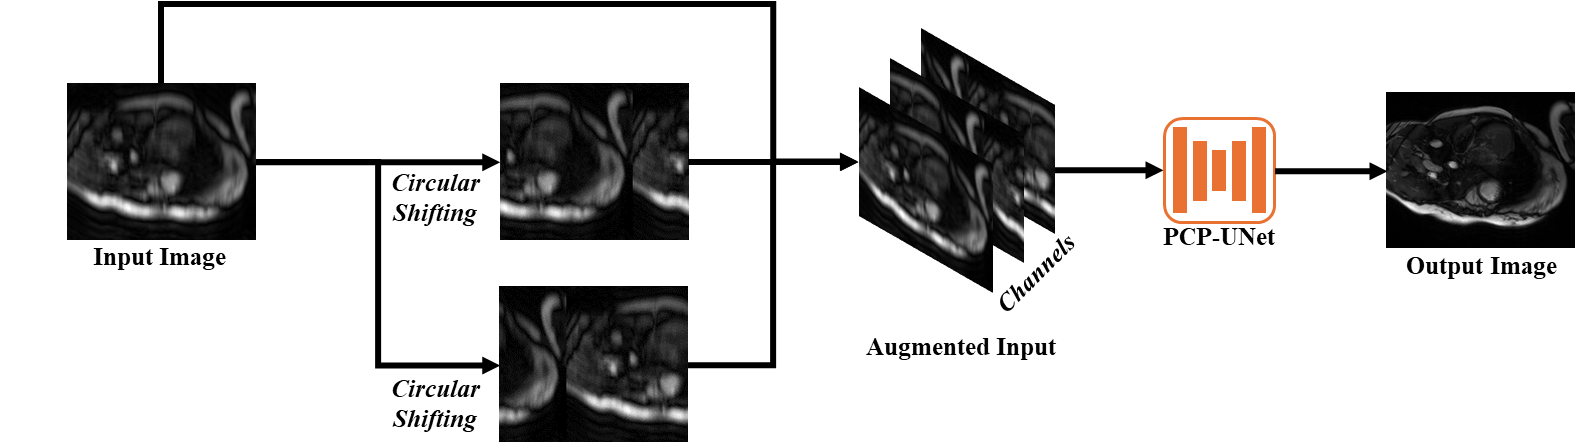

Figure 4: Enlarging receptive field via channel-shifting. Circular shifting along the sub-sampled direction(s) is performed to produce shifted replicas of the input image. The replicas are subsequently concatenated with the input along channel dimension to produce an augmented input, which is fed into a regular CNN with additional channels in its input layer.

2.4 Enlarging Receptive Field via Channel-Shift

Various sampling patterns result in different point-spread functions (PSF) in the image domain. Notably, the PSF can span the entire FOV due to the presence of a fully sampled center, as well as unevenly distributed sampling positions. This indicates a global receptive field is necessary to better distinguish between PSFs of different sampling patterns, which can be leveraged to improve image reconstruction quality. To efficiently enlarge the receptive field, we propose to augment the input image with circular-shifted replicas, which are then concatenated as additional image channels. The augmented input is fed into PCP-UNet with additional input channels (Fig. 4). With a sufficient number of shifted replicas, this channel-shifting can enable having aglobal receptive field, while accepting arbitrary input sizes. Channel-shifting has a minor computational overhead equivalent to adding an additional convolutional layer with multiple channels. Channel-shifting has no additional memory consumption when the number of input channel is not greater than the maximum number of channels in the hidden layers.